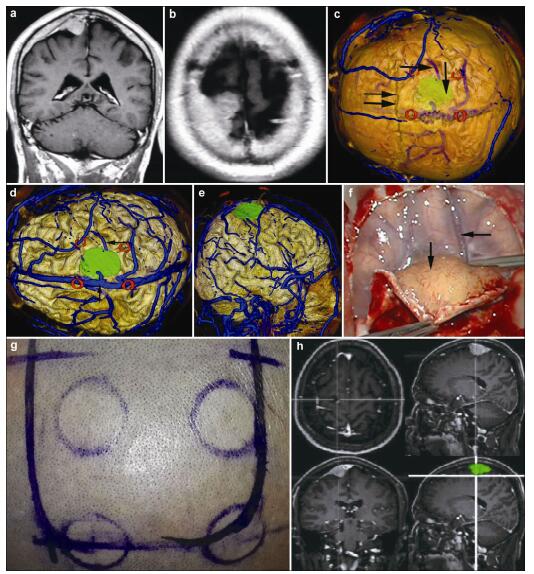

20170308095715  Figure 1 Magnetic resonance imaging, reconstruction images, surgical incision, and actual operative view in a 51-year-old male patient with a meningioma in right parietal lobe. (a, b) T1 enhancement scans: The tumor presented as homogenous enhancement. (c) 3D reconstruction (skull semitransparent): The tumor (vertical single arrow) located above lambdoidal suture (horizontal double arrow) and the superior cerebral veins (horizontal single arrow) are faintly visible. (d) 3D reconstruction (do not show the skull): On the surface of brain adjacent to the tumor are superior cerebral veins and superior sagittal sinus. (e) Sagittal cutting: The tumor is above the vein of galen and straight sinus. (f, g) The comparison of intraoperative situation and 3D reconstruction: The intraoperative situation is consistent with 3D reconstruction images. (h) Surgical incision.